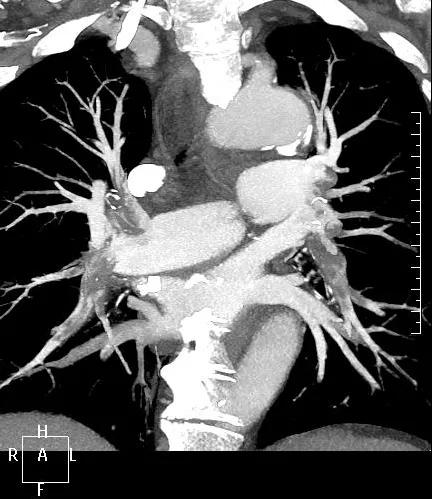

近日,一名港胞翁阿姨在我市突發(fā)急性肺栓塞,生命垂危。市二院在接到120出車指令后,迅速響應(yīng),患者入院后開通綠色通道,經(jīng)急診科、心內(nèi)科、介入科、重癥醫(yī)學(xué)科等多學(xué)科專家開展聯(lián)合會診,并于當(dāng)晚9點行“下腔靜脈、肺動脈造影+導(dǎo)管溶栓+濾器植入術(shù)”,患者終于轉(zhuǎn)危為安,經(jīng)后續(xù)治療與精心護理,病情逐漸穩(wěn)定,現(xiàn)已轉(zhuǎn)入普通病房。